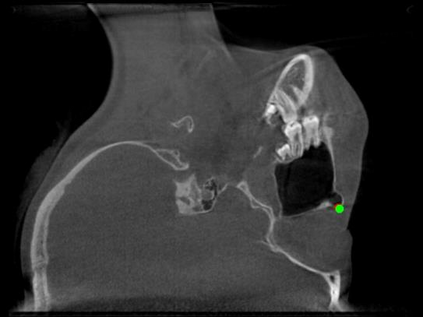

Detecting 3D landmarks on cone-beam computed tomography (CBCT) is crucial to assessing and quantifying the anatomical abnormalities in 3D cephalometric analysis. However, the current methods are time-consuming and suffer from large biases in landmark localization, leading to unreliable diagnosis results. In this work, we propose a novel Structure-Aware Long Short-Term Memory framework (SA-LSTM) for efficient and accurate 3D landmark detection. To reduce the computational burden, SA-LSTM is designed in two stages. It first locates the coarse landmarks via heatmap regression on a down-sampled CBCT volume and then progressively refines landmarks by attentive offset regression using multi-resolution cropped patches. To boost accuracy, SA-LSTM captures global-local dependence among the cropping patches via self-attention. Specifically, a novel graph attention module implicitly encodes the landmark's global structure to rationalize the predicted position. Moreover, a novel attention-gated module recursively filters irrelevant local features and maintains high-confident local predictions for aggregating the final result. Experiments conducted on an in-house dataset and a public dataset show that our method outperforms state-of-the-art methods, achieving 1.64 mm and 2.37 mm average errors, respectively. Furthermore, our method is very efficient, taking only 0.5 seconds for inferring the whole CBCT volume of resolution 768$\times$768$\times$576.